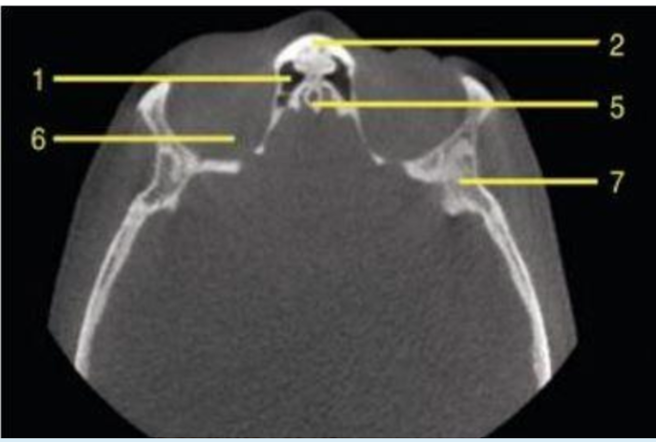

axial

what plane is this

C2 odontoid process

what is 43

coronoid process

what is 52

orbit

what is 6

submandibular fossa

identify 5